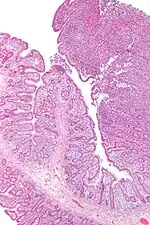

| Micrograph of an enteropathy-associated T-cell lymphoma (upper right of image), a type of T-cell lymphoma. H&E stain. | |